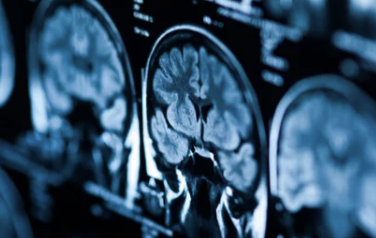

뇌경색 전조증상: 작은 신호가 생명을 살린다! 반드시 알아야 할 초기 징후 총정리

뇌경색은 갑작스럽게 찾아오는 질병처럼 보이지만, 사실은 몸이 보내는 경고 신호를 무시했을 때 발생하는 경우가 많습니다.

특히 뇌혈관이 막히는 전조 증상은 일시적으로 나타났다 사라지기도 하며, 이를 조기에 인지하지 못하면 심각한 후유증이나 사망으로 이어질 수 있습니다.

뇌경색은 뇌혈관이 혈전(피떡)이나 죽상경화(혈관 내 벽이 좁아지는 현상)로 인해 막혀서, 해당 부위 뇌조직이 혈액을 공급받지 못하고 괴사되는 질병입니다.